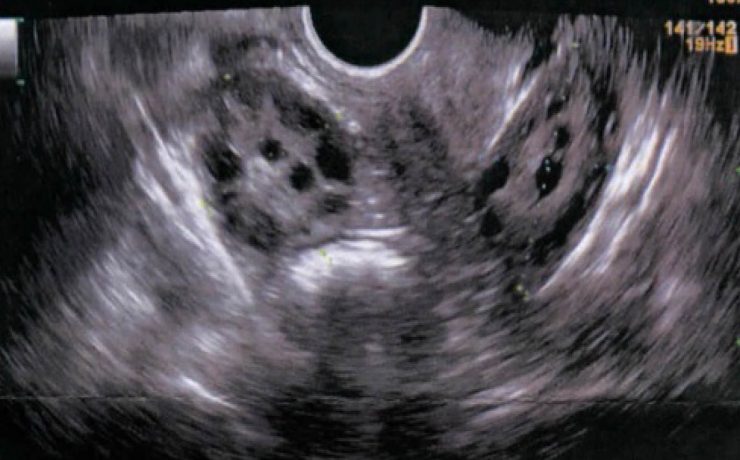

Más del 95% de las enfermedades biliares, son debidas a colelitiasis. En Estados Unidos su costo anual asciende a 8 millones de dólares, el 40% de los mayores de 40 años tiene colelitiasis y10 a 30% presentaran síntomas. 11% de la población adulta de E.U.A. Tiene cálculos biliares y esta